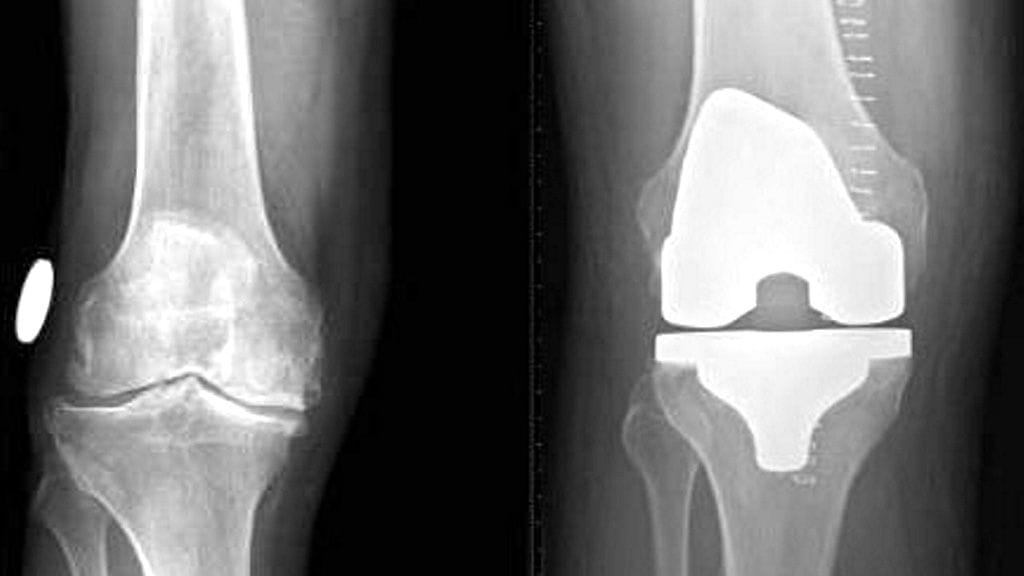

Rintarauhasen leikkausjonossa noin joka kolmas oli jonottanut yli lain rajan (180 vrk). Kyse on myös priorisaatiosta, hampaiden poistoon, polven/lonkan tekoniveleen ja kaulan/selkärangan luudutukseen joka neljäs potilas. Priorisaatio näkyy.

Ylipäätänsä kaikista erikoisaloista eniten potilaita odottaa polven tai lonkan tekonivelleikkaukseen (yli 10 000 potilasta) ja kaihileikkaukseen (yli 12 000 potilasta).

Esimerkiksi haastattelemamme helsinkiläinen potilas on ollut polven tekoniveljonossa pian puolitoista vuotta eikä hän anna hyvinvointiyhteiskunnan toimivuudelle hyviä pisteitä.